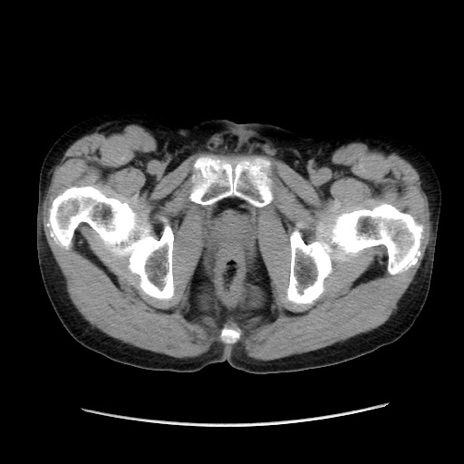

症例37(横断像)

冠状断像

【症例】40歳代 男性

【主訴】腹痛

【現病歴】4時間ほど前に電車に乗車中に臍部上より腹痛出現。徐々に増悪し起立困難となり、救急外来受診。生ものは数日食べていない。今朝お雑煮を食べた。

【身体所見】BT 36.8℃、BP 117/84mmHg、HR 91/min、SpO2 97%、苦悶様、腹部:臍上部広範囲圧痛あり、反跳痛±

【データ】WBC 8100、CRP 0.03